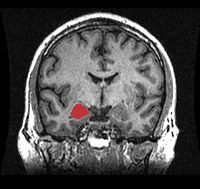

A new study examining the brain structure and activity of combat veterans with PTSD may help explain why some people experience symptoms of PTSD much more severely than others. Certain areas of the brain involved in learning and emotional response, most noticeably the amygdala, were meaningfully different in veterans with more severe symptoms. For more information about this study, please visit the NIH website.